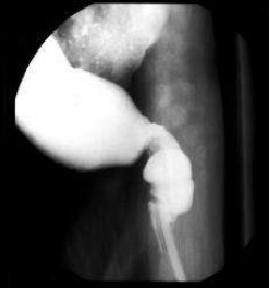

Valvule ileo-coecale :

Image radiologique normale |

1 - Anse ileale

2 - Valvule

3 - Coecum |